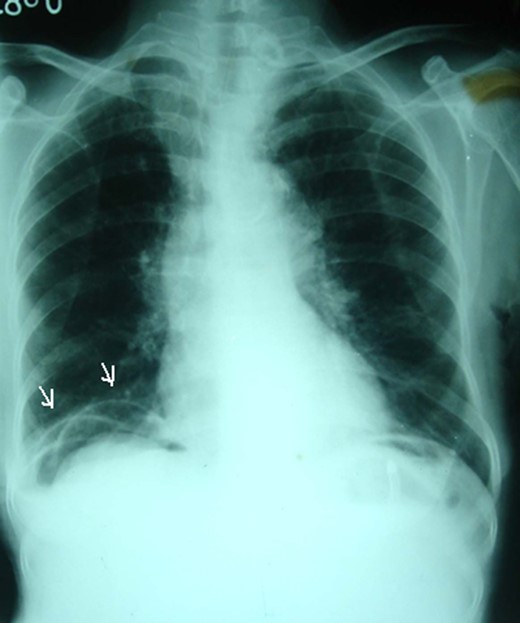

Plain supine abdominal radiograph showed features of small bowel obstruction. However, a plain chest radiograph taken in erect position showed radiolucent shadow under the right dome of the diaphragm, first simulating pneumoperitoneum (Fig. 1). The impression of free gas under the diaphragm was very much supported by the clinical finding of obliterated liver dullness. However, on careful examination of the radiograph, few semilunar radio-opaque linings could be seen, which could be walls of bowel loops (Fig. 2). She was diagnosed as acute intestinal obstruction, probably Chilaiditi's syndrome: we thought of obstruction due to herniation into the hepatodiaphragmatic space.

Careful examination showing semilunar opaque lines which were walls of small bowel loops (arrows).